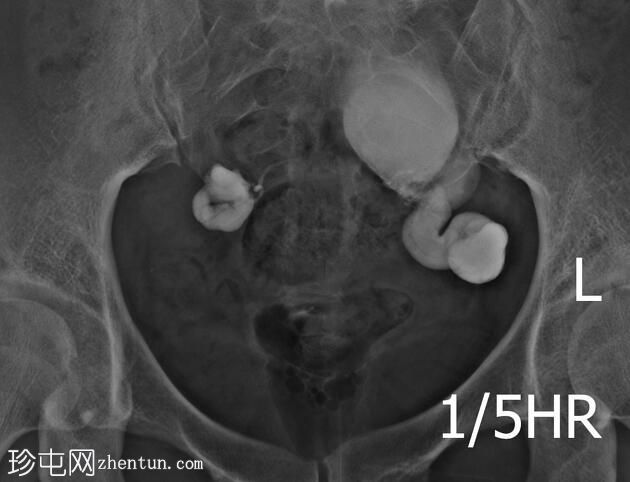

右侧输卵管扩张并充满液体,无腹膜溢出,提示输卵管积水及输卵管阻塞。

左侧输卵管亦扩张并充满液体,伴有造影剂残留及少量溢出,提示输卵管积水及输卵管阻塞。

此外,左侧盆腔内,位于输卵管上内侧,可见大量分隔的造影剂积聚,并伴有盆腔输卵管周围粘连。